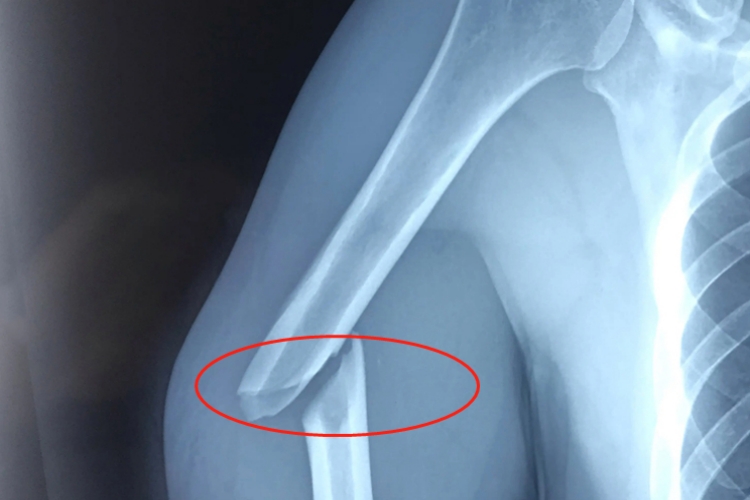

患者手臂骨折后,X线检查结果中局部会出现不整齐样断面,断端间可呈不规则透明线,临床上称为骨折线。同时,也会出现明显畸形、肿胀、疼痛等自觉症状。

患者手臂骨折后,无移位或稳定型骨骺分离可以遵医嘱进行三角巾悬吊,然后开始功能锻炼,无需手术治疗。对移位明显的骨折可采用切开复位,缝合固定或用克氏针交叉固定。